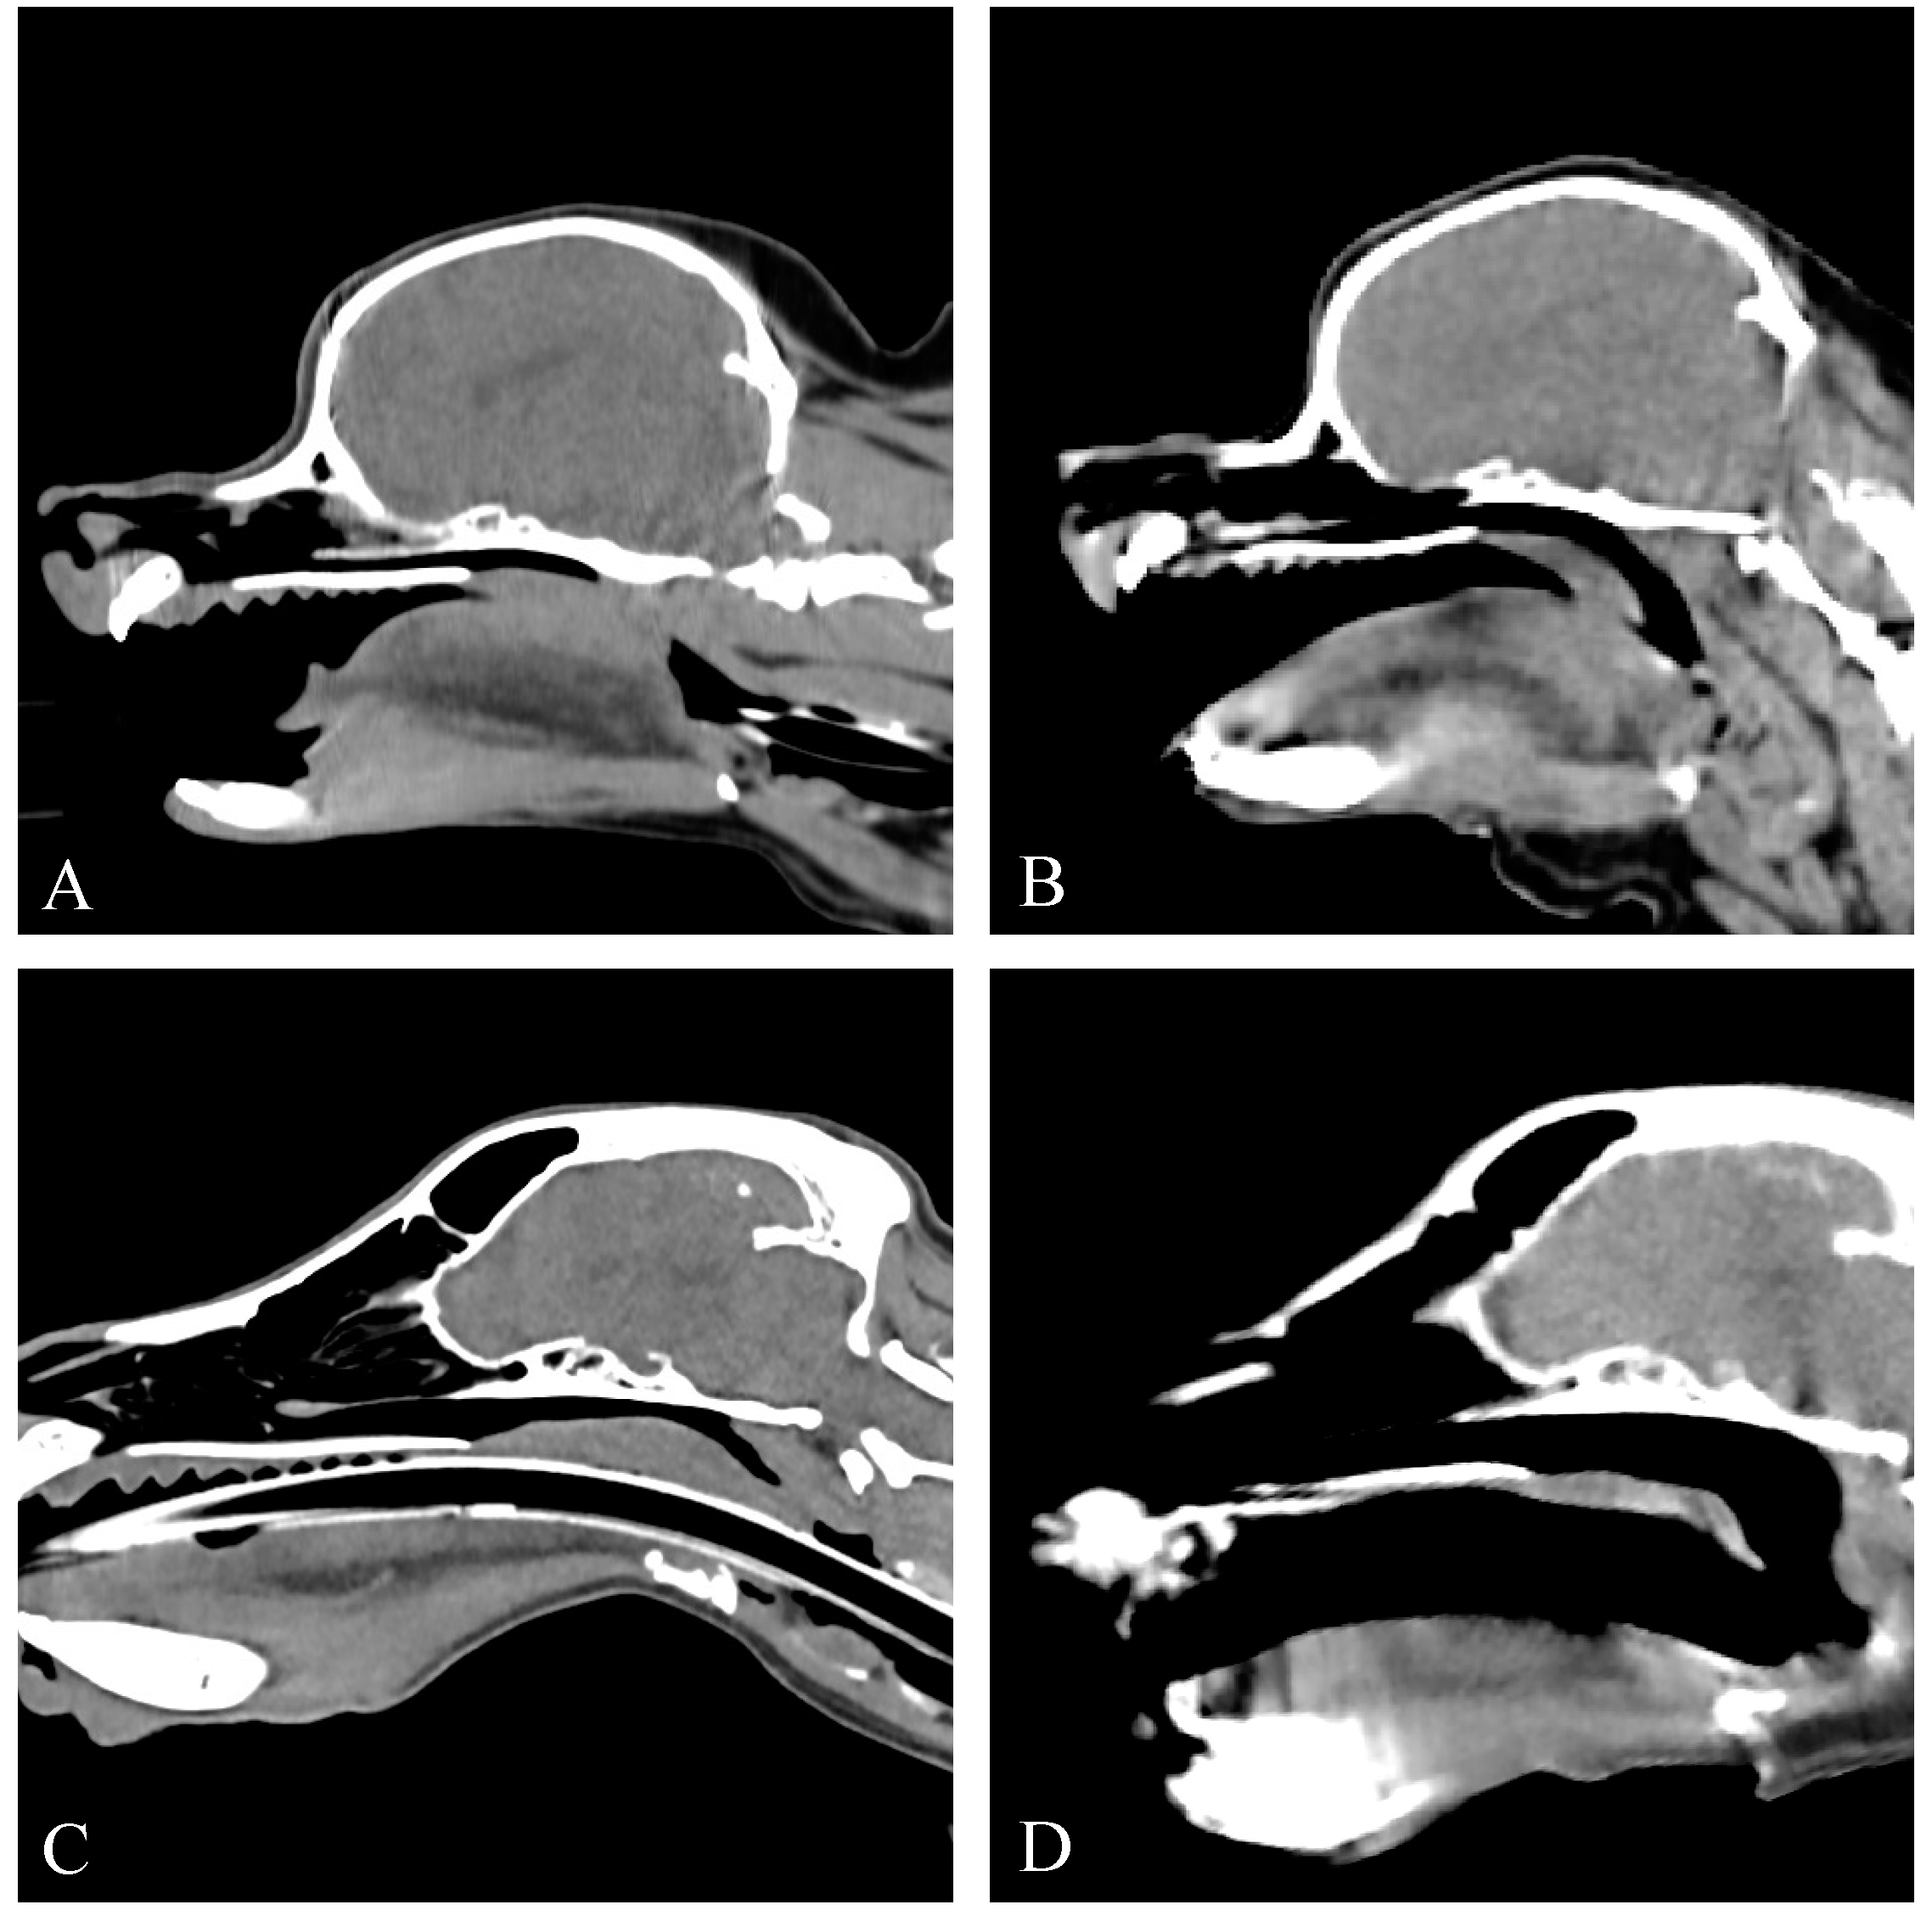

3.3.3. Group III

The CT provided diagnostic images for all six patients for the evaluation of the soft palate and nasopharynx, with mild motion artefacts in one patient, and moderate motion artifacts in one patient. Three of the six dogs had an overlong soft palate (cases 8, 12 and 13). Thickening of the soft palate was assessed as normal (n = 3) and mild (n = 3) based on the extent of nasopharyngeal obstruction. An open rima glottis was present in all six dogs. In one dog (case 12), severe nasopharyngeal narrowing was evident (Figure 5). At a subsequent CT scan following improvement in clinical signs following treatment with anti-inflammatory corticosteroids, normal nasopharyngeal dimensions were now present (Figure 5). While the head position appeared consistent between the two scans, and no motion artefact was detected during image acquisition to suggest swallowing, the potential for this to be artefactual cannot be fully discounted. In another dog (case 4), a prior CT scan conducted under general anaesthesia had revealed moderate soft palate thickening, causing nasopharyngeal narrowing. However, the conscious CT scan demonstrated a reduction in palate thickness and resolution of the nasopharyngeal narrowing (Figure 5). The patient had received anti-inflammatory corticosteroid treatment in the time period between the two scans.

Figure 5. Sagittal non-contrast CT images of the skull of two patients assessed for nasopharyngeal narrowing (group III). (A) Case 12, CT under anaesthesia showing severe nasopharyngeal narrowing. (B) Case 12, conscious CT showing resolution of nasopharyngeal narrowing following steroid treatment. (C) Case 4, CT under anaesthesia showing moderate soft palate thickening and caudo-dorsal nasopharyngeal hypertrophy causing nasopharyngeal narrowing. (D) Case 4, conscious CT showing normal palate thickness and resolution of nasopharyngeal narrowing following steroid treatment. Window width, 400 HU; window level 40 HU; 1 mm slice thickness.